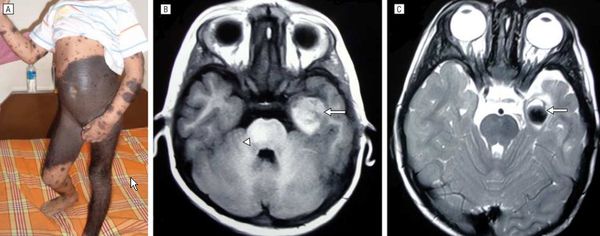

Проанализирован случай сложной морфологической верификации результатов гистологического и иммуногистохимического исследований гигантского очага в коже затылочной области головы, шеи, крупного очага в правой доле печени и многочисленных мелких очагов в головном мозге, на коже туловища и конечностей у доношенного новорожденного ребенка.

При морфологическом исследовании обращала на себя внимание неправильная форма головы. Под кожей в затылочной области определялось гигантских размеров полусферическое образование бледно-коричневого цвета размером 13×10×2,5 см с двумя участками перфорации длиной 2,5 и 10 см. Ткань опухоли мягкой консистенции буро-коричневого цвета, на разрезе губчатого вида, мелкокистозная, формирует несколько камер. Образование плотно врастает в кожу и значительно истонченную чешую затылочной кости. На всей поверхности кожи отмечались многочисленные мелкие пятна размером до 0,3 см кофейно-серого цвета типа невусов. На разрезе в правой доле печени определялись очаг темно-коричневого цвета округлой формы размером 1,5×1,0 см, мелкие очаги коричневатого цвета с четкими контурами до 0,2 см в белом веществе головного мозга.

При гистологическом исследовании образование затылочной области представлено субэпидермально располагающейся опухолью, прорастающей надкостницу, но не затрагивающей придатки кожи. В ткани опухоли определялись немногочисленные фиброзные прослойки и сосудистые щели. Опухолевые клетки малых размеров с округлыми ядрами со слабым полиморфизмом содержали железонегативный пигмент. Очаг в ткани печени имел подобное гистологическое строение, очаги в ткани головного мозга были представлены нагруженными пигментом эндотелиальными клетками. Остальные органы без патологических изменений. При иммуногистохимическом (ИГХ) исследовании опухоли головы маркер пролиферативной активности Ki-67 экспрессировал 10—25% опухолевых клеток. Экспрессия антигенов эндотелиальных клеток, отражающая процессы неоангиогенеза в опухоли CD31, CD34, негативна. В связи с необходимостью верификации гистологических препаратов опухоли проведено совместное консультирование специалистов детского онкологического центра в формате телеконференции с D. Harms, проф. клиники Университета им. Кристиана Альбрехта, г. Киль, Германия. Согласно заключению специалистов-онкологов, патоморфологически опухоль воспроизводит структурные элементы артериовенозных анастомозов, представляя собой беспорядочно переплетающиеся сосуды, окруженные эпителиодными (гломусными) клетами. Вследствие неоднозначности гистологической картины, которая не позволяла дифференцировать сосудистую и меланоцитарную опухоль, рекомендовано проведение расширенной ИГХ-панели для определения гистогенеза опухоли. После дополнительных исследований получены следующие данные: клетки опухоли интенсивно экспрессируют Vimentin, HMB45, S100. В то же время экспрессия PCK (Рan Cytokeratin), α-актина, синаптофизина, NSE, Glut1 негативна. На основании всех полученных данных сделано заключение: опухоль доброкачественная, состоит из клеток меланоцитарного ряда и не имеет эпителиального, мышечного, нейрального компонентов [7, 8].

Таким образом, учитывая вышеизложенное, можно заключить, что на пренатальном этапе диагностика была затруднена из-за ограничения методов визуализации после рождения и краткосрочного пребывания ребенка в стационаре. При патолого-анатомическом исследовании было невозможно сделать окончательный вывод о природе опухоли в связи с большим количеством мелких сосудов и наличием клеток, расцененных как гломусные. Потребовалось определение тканеспецифических маркеров и белков HMB45, S100, характерных для клеток меланоцитарного ряда. По совокупности клинических данных, результатов морфологического исследования, включавшего постановку ИГХ-реакций, верифицировано основное заболевание — врожденный меланоцитарный невус.